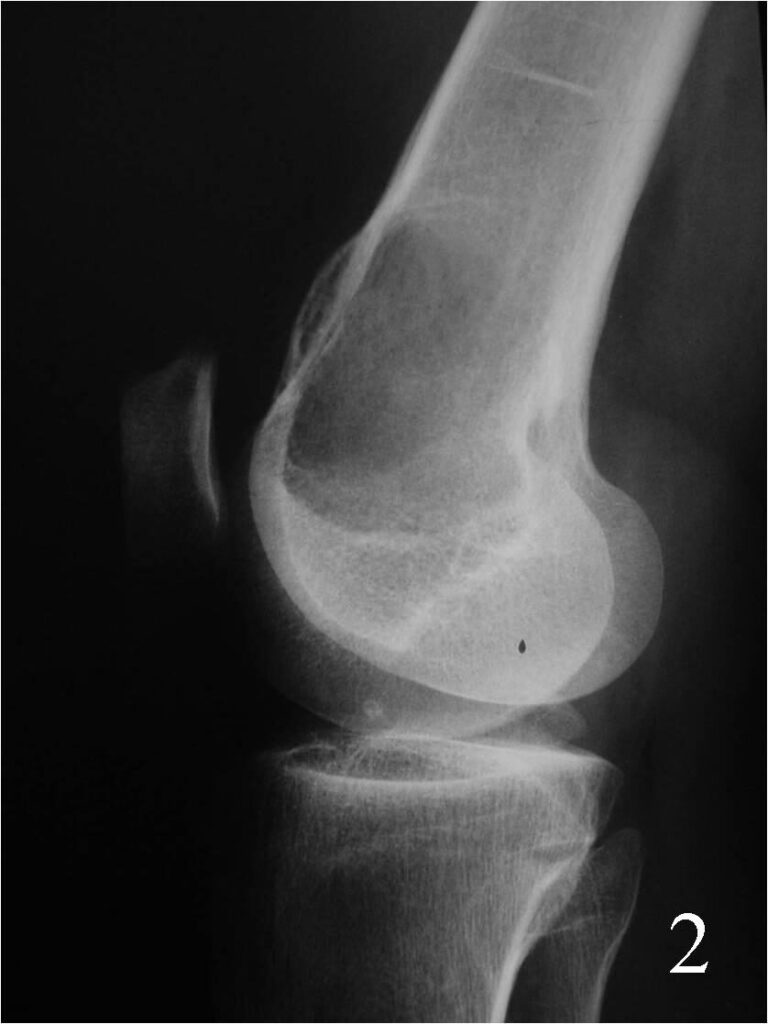

- Can arise in the medullary portion, but can be eccentric (Fig. 2)

Fig. 2 Lateral Xray of the knee showing a lytic lesion, notice the expansible lesion on the anterior cortex